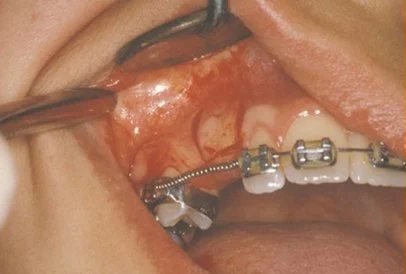

In a simple surgical procedure performed in the surgeon’s office, the gum on top of the impacted tooth will be lifted up to expose the hidden tooth underneath. If there is a baby tooth present it will be removed at the same time. Once the tooth is exposed, the oral surgeon will bond an orthodontic bracket to the exposed tooth. The bracket will have a miniature gold chain attached to it. The oral surgeon will guide the chain back to the orthodontic arch wire where it will be temporarily attached. Sometimes the surgeon will leave the exposed and impacted tooth completely uncovered by suturing the gum up high above the tooth, or making a window in the gum covering the tooth. Most of the time the gum will be returned to its original location and sutured back with only the chain remaining visible as it exits a small hole in the gum.

Shortly after surgery (1-14 days) the patient will return to the orthodontist. A rubber band will be attached to the chain to put a light eruptive pulling force on the impacted tooth. This will begin the process of moving the tooth into its proper place in the dental arch. This is a carefully controlled, slow process that may take up to a full year to complete. Remember, the goal is to erupt the impacted tooth and not to extract it. Once the tooth has moved into the arch in its final position, the gum around it will be evaluated to make sure it is sufficiently strong and healthy to last for a lifetime of chewing and tooth brushing. In some circumstances, especially those where the tooth had to be moved a long distance, there may be some minor “gum surgery” required to add bulk to the gum tissue over the relocated tooth so that it remains healthy during normal function. Your dentist or orthodontist will explain this procedure to you if it applies to your specific situation.